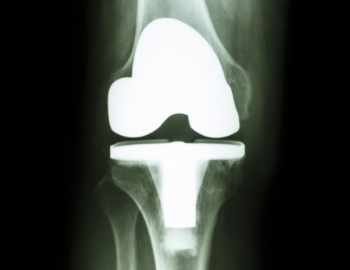

X-ray of a patient's knee with a total knee replacement. Only the metal shows up on X-ray.

A total knee replacement (TKR) is a replacement of the femoral and tibial surfaces of the knee joint, and generally also part of the patella, with metal and plastic. Page updated February 2024 by Dr Sheila Strover (Clinical Editor)

Total knee replacement usually implies replacing all three of the articulating areas in the knee with implants comprised of metal and plastic. A femoral and a tibial implant replace the two joint surfaces between femur and tibia, and a patellar implant replaces the joint surface between femur and patella.

Between the two larger implants is a plastic spacer, which effectively replaces the two menisci.